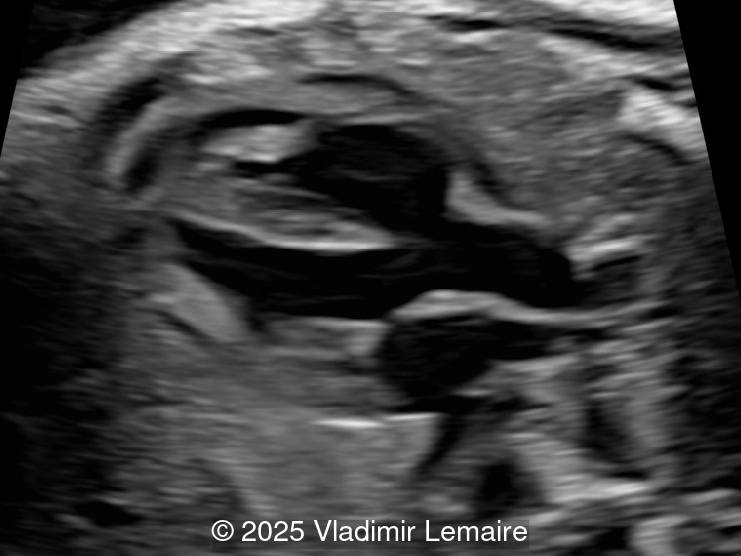

3D spatiotemporal image correlation (STIC) ultrasound volume at the level of the five-chamber view. Note the presence of a VSD and a dilated aorta.

Image 1 3D spatiotemporal image correlation (STIC) ultrasound volume at the level of the five-chamber view. Note the presence of a VSD and a dilated aorta.

3D spatiotemporal image correlation (STIC) ultrasound volume at the level of the five-chamber view.

Image 2 3D spatiotemporal image correlation (STIC) ultrasound volume at the level of the five-chamber view.